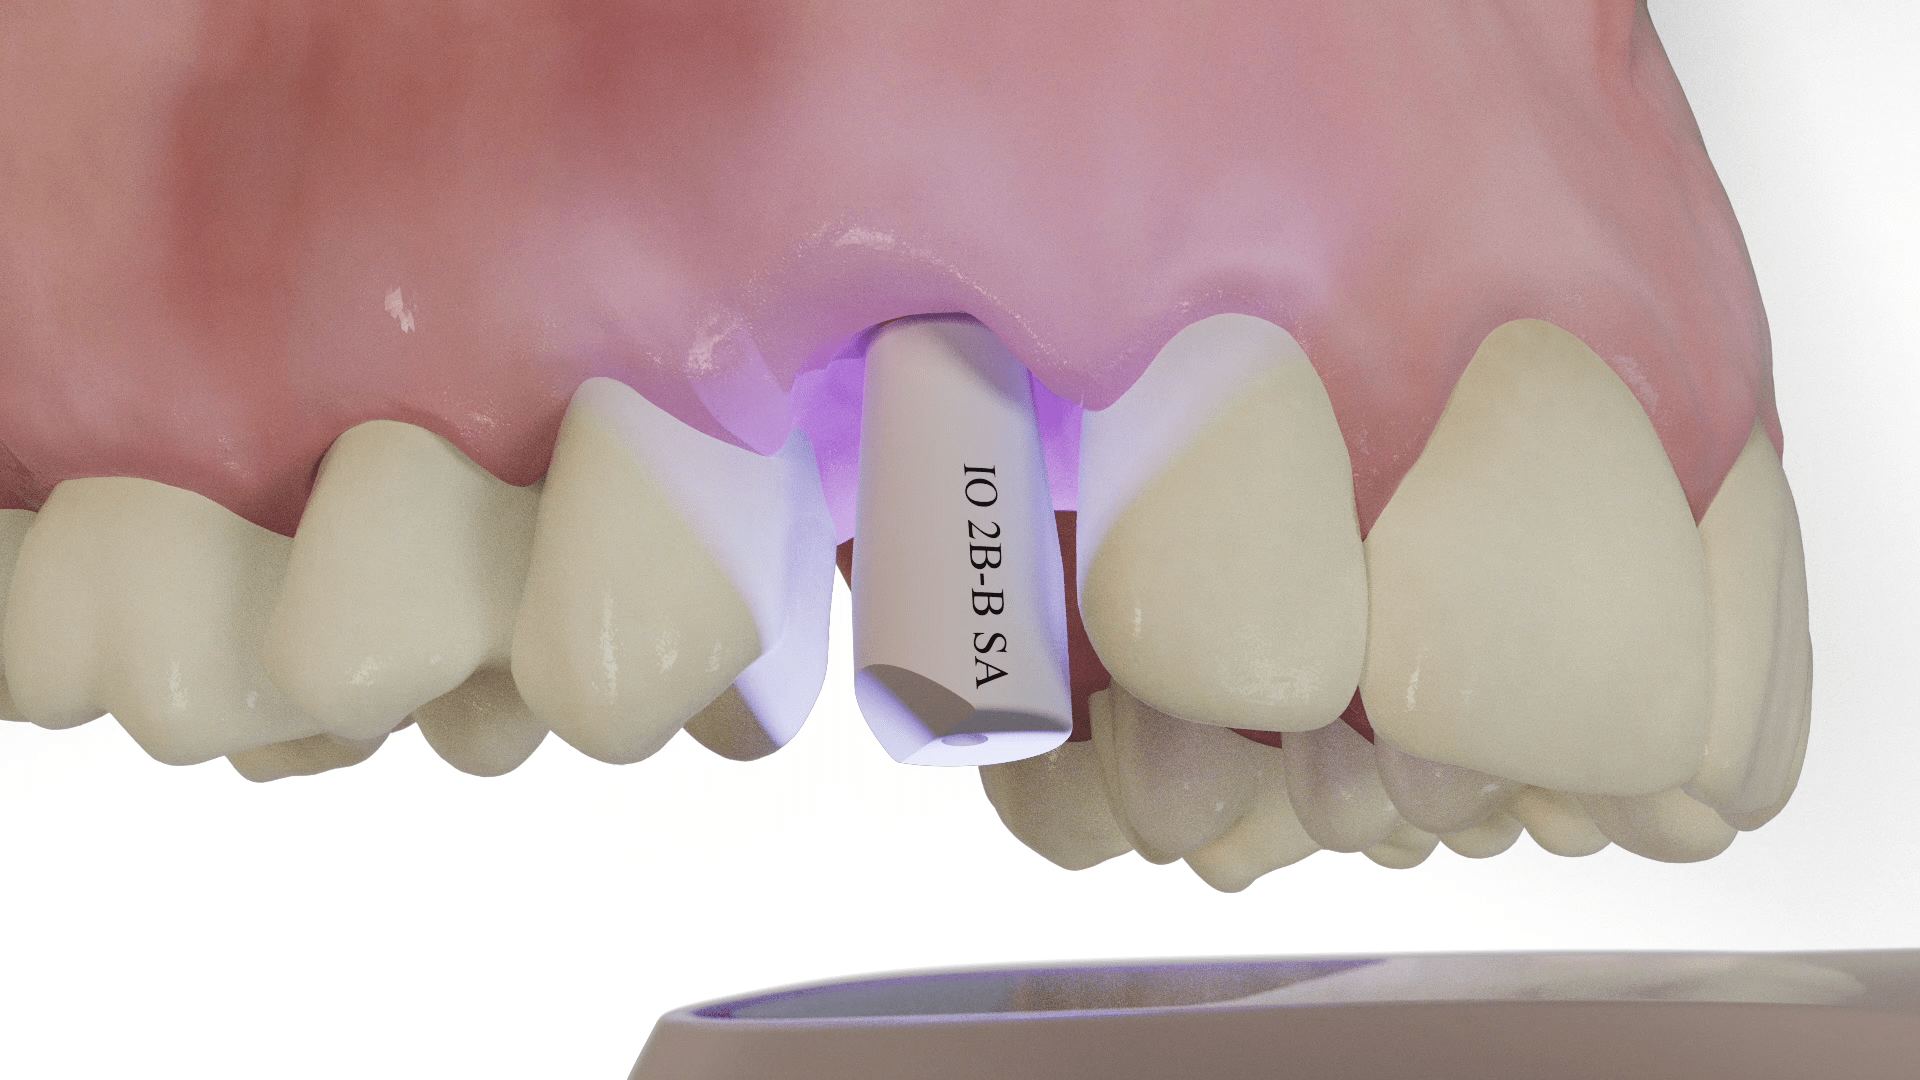

From m6cadcam-dental.com

PEEK titanium intra oral dental implant scan body to take digital Dental Scan For Implants Dentists use cbct scans as a diagnostic tool to make implant treatment as accurate as possible. This type of ct scan uses a cone. This is where dental ct scans come in. Allow your dentist to plan your implant. These scans also serve as a powerful tool for determining whether you are a suitable candidate for dental implants in the. Dental Scan For Implants.

From www.cad-ray.com

digital implant scanbody Dental Scan For Implants This is why a ct scan of the jaw bone, which. This type of ct scan uses a cone. Ideally an implant site has at least 7 mm of. Dentists use cbct scans as a diagnostic tool to make implant treatment as accurate as possible. Allow your dentist to plan your implant. These scans also serve as a powerful tool. Dental Scan For Implants.